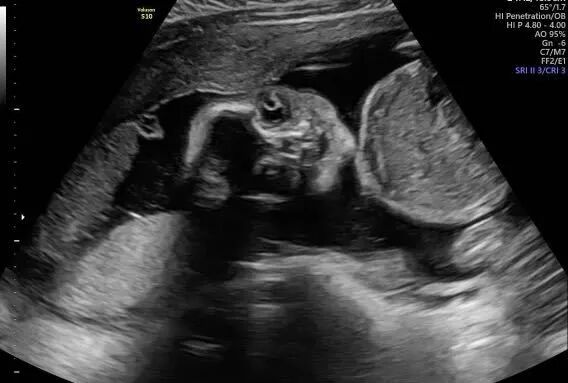

宝宝接近四个月的时候,爱妈Y再次进行了B超检查,此次检查清晰显示出一个健康可爱的女宝宝。爱妈随即将B超照片发送给准妈妈,并满心欢喜地赞叹宝宝的可爱。看到宝宝健康成长,准妈妈既感动又高兴,对爱妈的细心照料表示深深的感激。 准父母成功匹配后,我们会为双方建立一个交流群,这样准父母和爱妈可以方便地进行沟通。在这个群里,爱妈和我们的客服团队会定期更新检查结果和宝宝的成长情况。我们都非常期待下次见到宝宝的时刻!